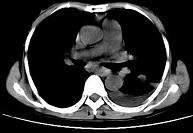

问题 女,55岁,胸痛伴咯血丝痰1周,胸部CT如图,最可能的诊断为 ( )

选项 A.转移性肺癌 B.左侧周围型肺癌并肺内转移 C.左侧中央型肺癌并肺内转移 D.多发性肺脓肿 E.结节病

答案 B